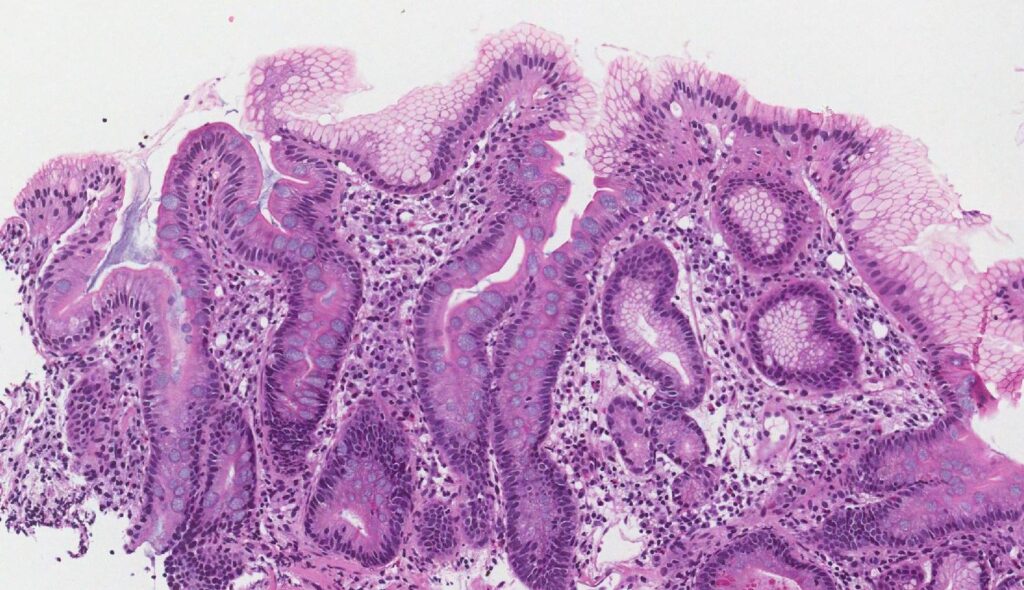

La metaplasia epitelial plana-cilíndrica, como en el caso de reflujo gastroesofágico (esófago de Barrett), el epitelio plano estratificado sin estrato córneo del tracto inferior del esófago puede sufrir una transformación metaplásica en epitelio cilíndrico simple similar al intestinal que contiene células calciformes.